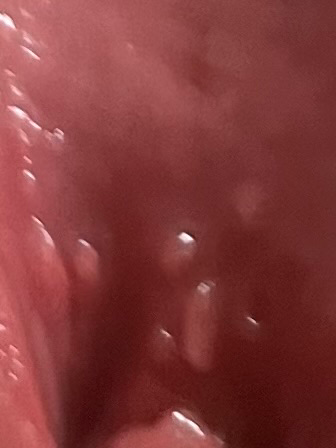

생리하는 도중 관계를 한 번 가졌는데 그 뒤로 가려움증이 있고 생식기가 빨갛고 부은것같아서 확인해보니 질 입구 위 쪽에 뭔가 오돌토돌한게 5개 정도 난 것 같은데 성병인걸까요

• 1번 째 사진